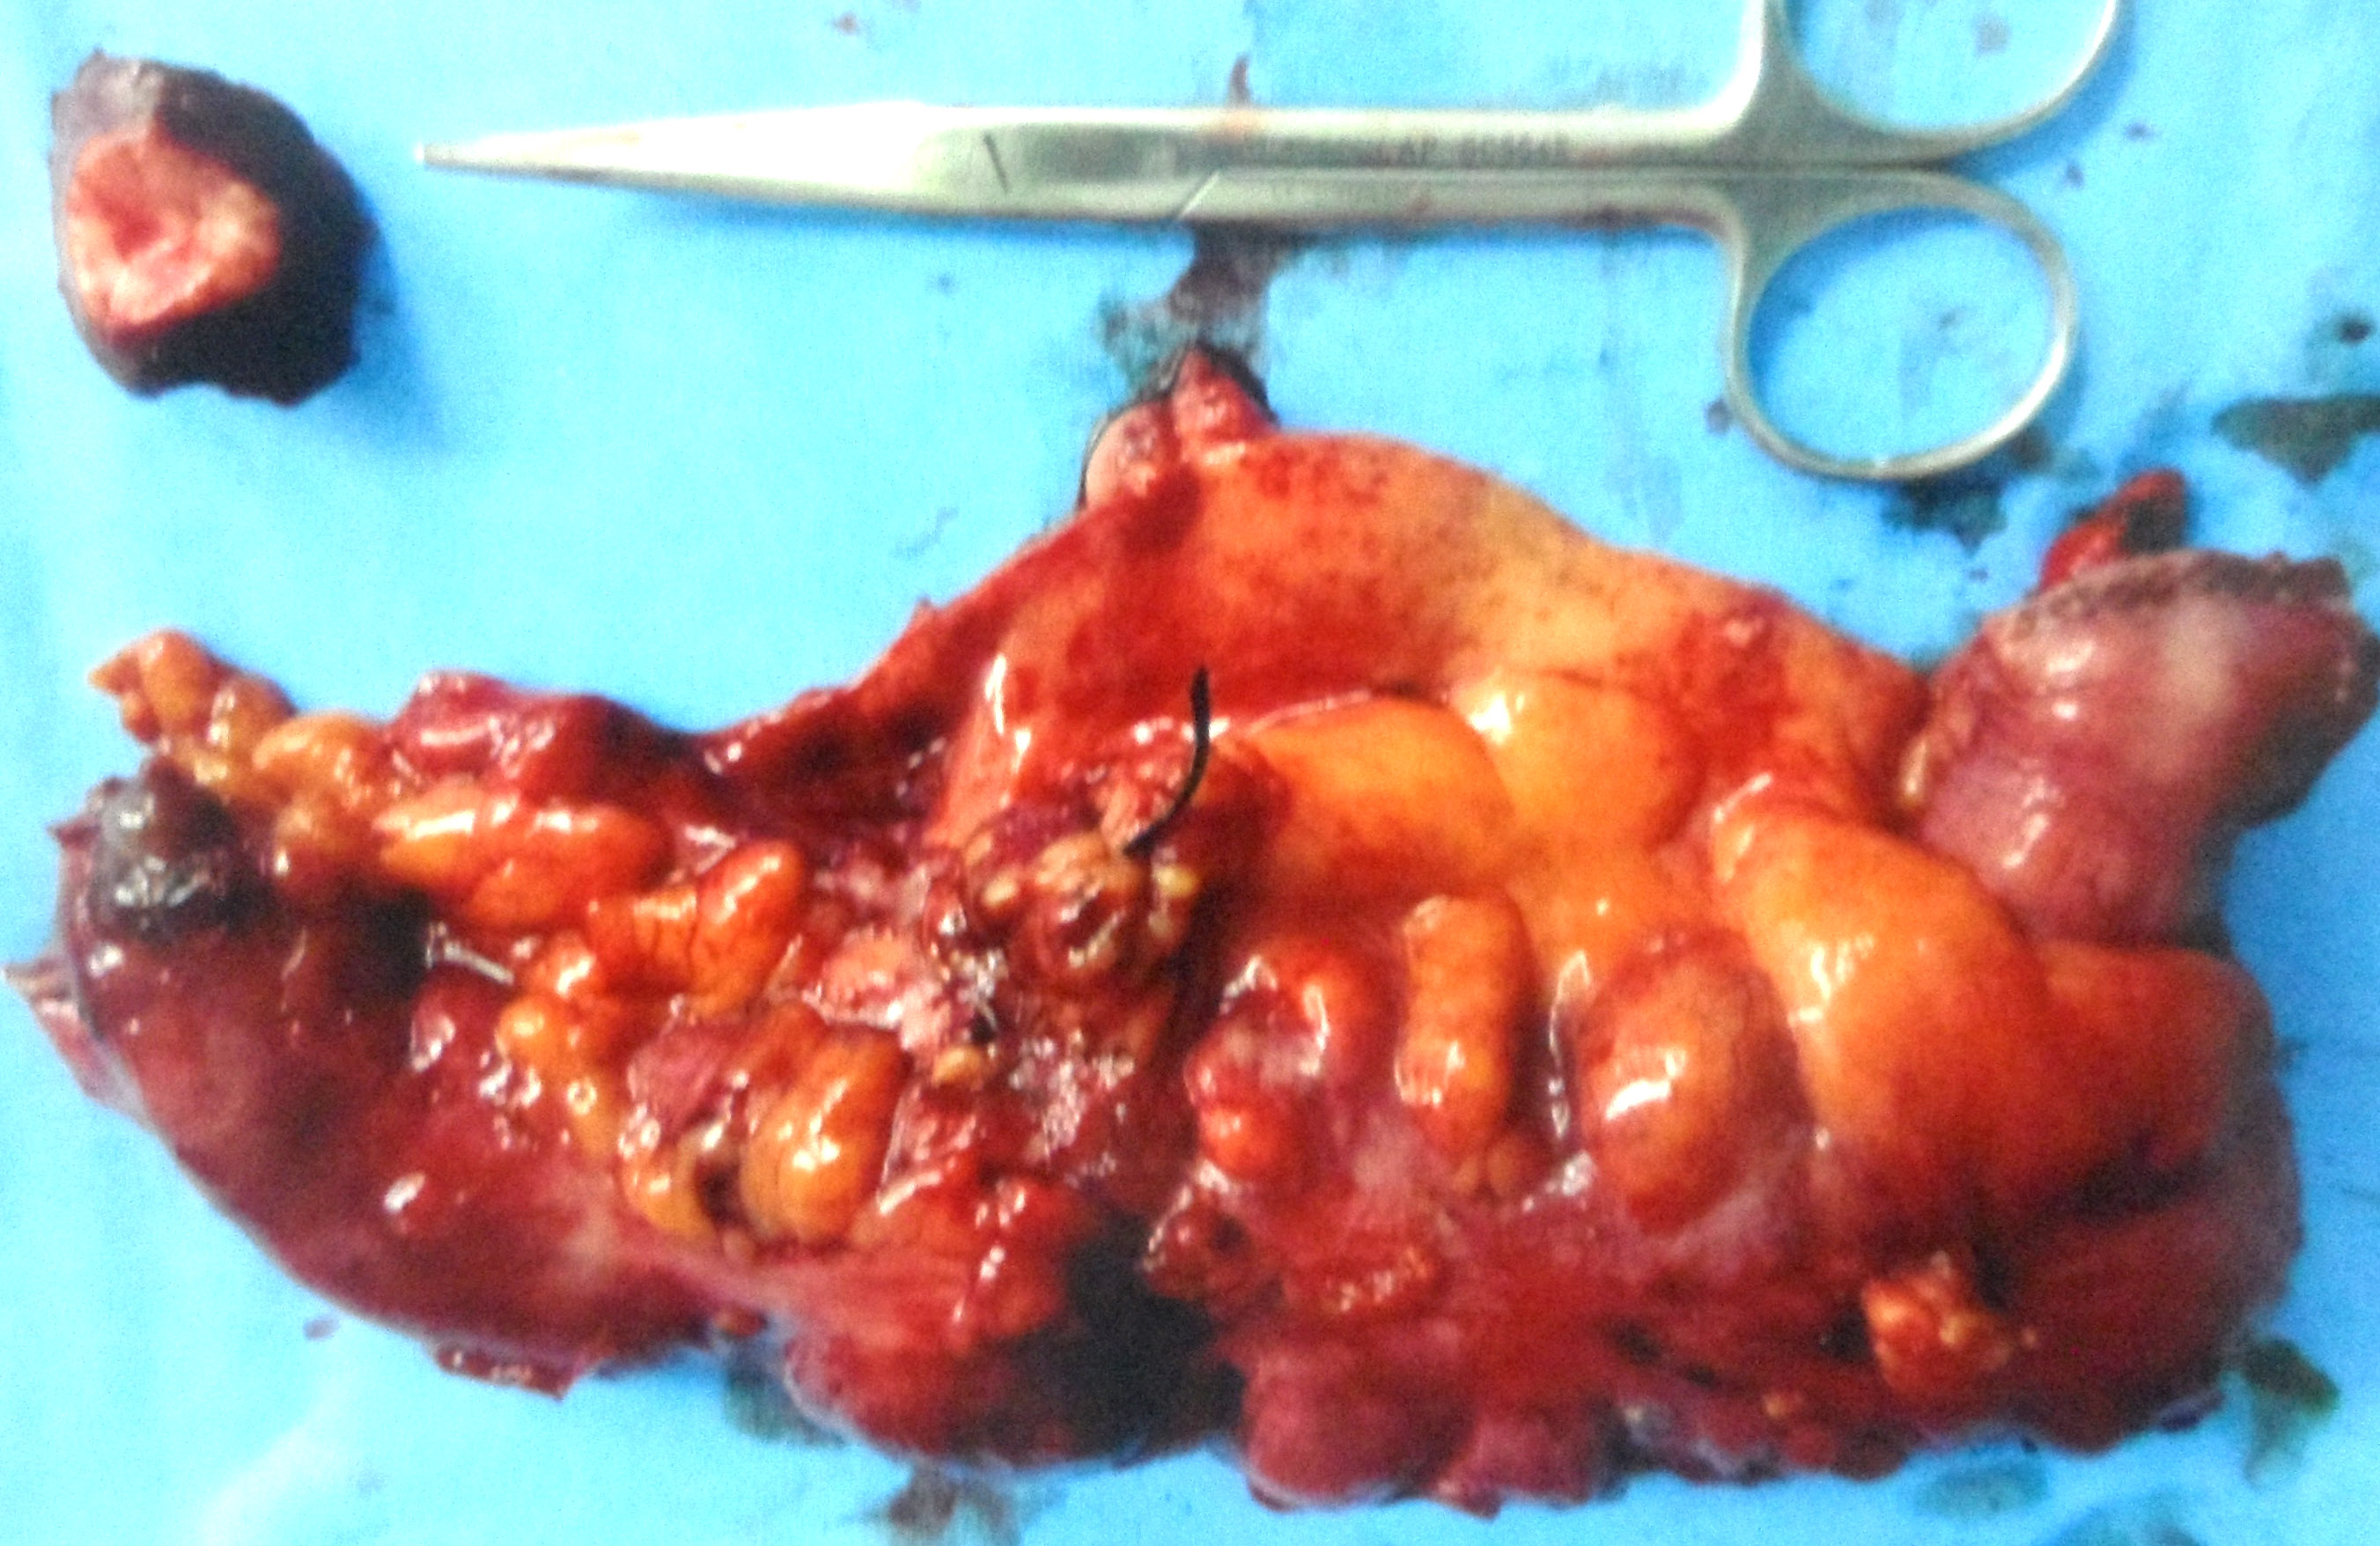

On 26 June 2018, CHK underwent another operation (right hemicolectomy) in a private hospital in Kuala Lumpur.

The surgeon removed about 17 cm of the colon, in addition to the omentum. Unfortunately, the surgeon did not do anything to the two metastatic liver nodules.